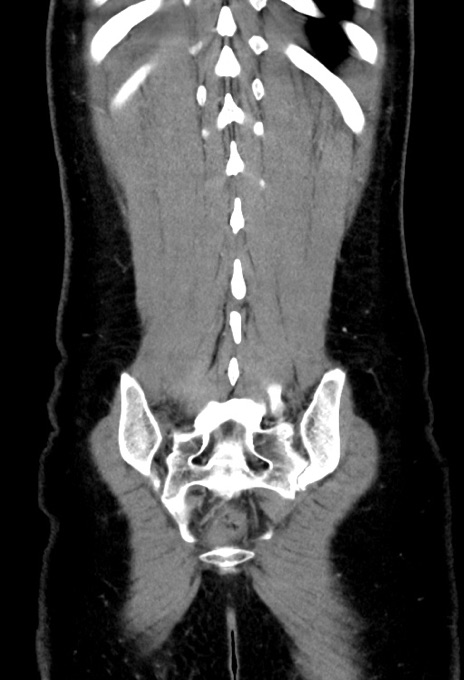

横断像